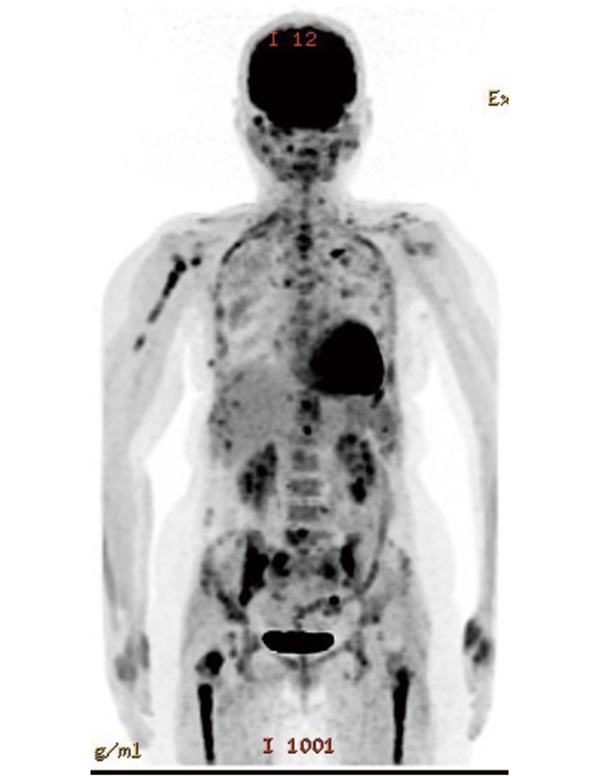

がんは進行すると全身のさまざまな臓器に転移しますが、骨は転移しやすい臓器の一つです。骨転移は主に肺がん、乳がん、前立腺がんでみられますが、疼痛、病的骨折、脊髄圧迫による神経障害、高カルシウム血症などさまざまな合併症を起こします。その結果、がん治療が続けられず治療成績を悪化させたり、本人の生活の質(QOL)を低下させうる、注意すべき病態です。

骨転移を抑制するためには、もとのがんの治療とあわせて、支持療法として骨修飾薬の適切な使用が重要です。ビスフォスフォネート薬であるゾレドロン酸(ゾメタ®)および抗RANKLモノクローナル抗体製剤であるデノスマブ(ランマーク®)が使用されます。日本ではいずれも悪性腫瘍の骨転移または多発性骨髄腫の骨病変に保険承認となっていますが、多発性骨髄腫では抗腫瘍効果(がんの抑制効果)も示されており、より積極的に導入されます。